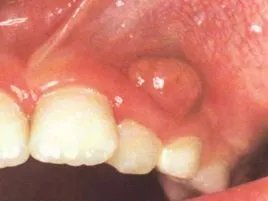

一例根尖周脓肿 - 口腔专业讨论版 -丁香园论坛

急性根尖周炎

四岁宝宝牙龈发炎鼓包医生说是根尖囊肿还有龋齿